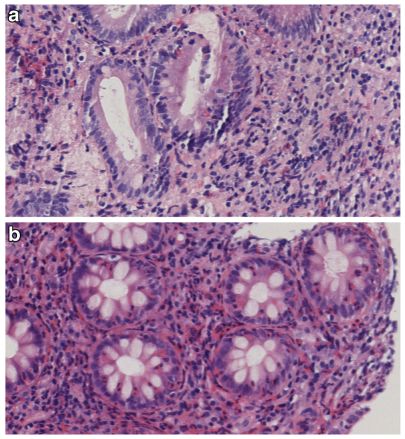

因此,确定病理性嗜酸细胞浸润的截止点应考虑肠道活检的定位。在十二指肠,大多数研究使用20个嗜酸性粒细胞/高倍视野(×400)诊断EE。除了固有层中的嗜酸性粒细胞外,组织学上有利于EE的其他标志物还有上皮或肌肉层中的嗜酸性粒细胞、嗜酸性粒细胞脱粒(由于嗜酸性粒细胞活化导致嗜酸性粒细胞主要碱性蛋白的细胞外沉积)、绒毛萎缩、隐窝增生或脓肿以及上皮变性/再生因子的变化(图1)。

图1 嗜酸性肠炎患者的组织学表现。a.女性嗜酸性肠炎患者十二指肠嗜酸性浸润。嗜酸性粒细胞对固有层的密集浸润、脱粒迹象和嗜酸性粒细胞对十二指肠上皮的浸润(苏木精-伊红染色,放大倍率×40)。b.男性嗜酸性肠炎患者结肠嗜酸性细胞浸润。嗜酸性粒细胞呈红色,核呈分叶状。图中,不仅固有层中嗜酸性粒细胞数量增加,而且结肠上皮中嗜酸性粒细胞的异常存在和脱粒迹象(细胞外呈红色)(苏木精-伊红染色,放大倍率×40)。